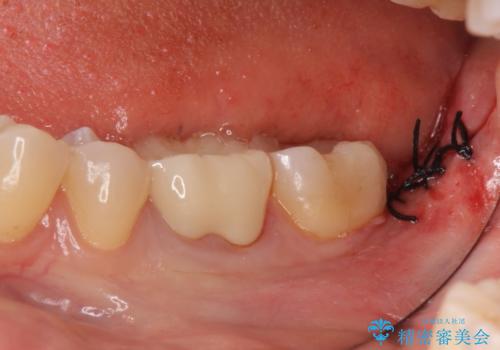

ただし、元のインレーが遠心マージンが縁下だったため、矯正治療後に歯ぐきの厚みを減らして、しっかり歯ぐきの上にマージンラインが来るように整える手術(ディスタルウェッジ)を行いました。

手術後、きちんとマージンラインが歯肉の上に来た状態で、セラミックインレー修復を行いました。

レーザーや電気メスで分厚い歯肉を焼いても一時的で、やがてまた元のように歯ぐきが上まで増殖しますので、今回は骨の厚みも調整し、7番の遠心を出来るだけ下げました。